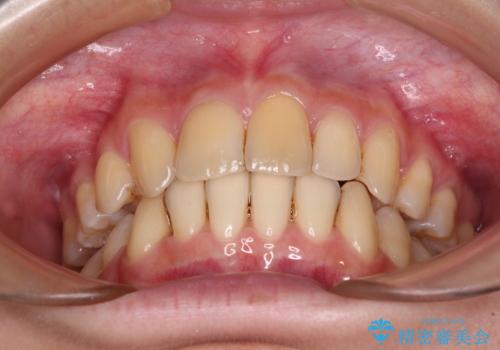

- 上下の出っ歯を気にして来院された患者様です。

口元を積極的に引っ込めるために、上下左右の小臼歯を4本抜歯することとしました。

右上前から2番目の歯が欠損しているため、①矯正治療により欠損部にスペースを作りインプラント補綴を行って前歯を左右対称に揃える、②左右非対称となるが、欠損補綴を行わずに排列する、のいずれかとなりますが、患者様と相談の上②にて矯正治療を行うこととしました。

変則的な歯列であったため、奥歯がしっかりと咬み合うのか、前歯はしっかりと排列できるのかと不安ではありましたが、結果としてはきれいに整った歯列にて終了することができました。